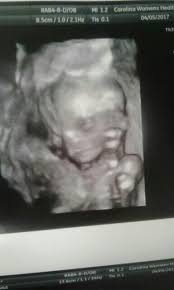

5 weeks 2 days posted by: Six full weeks is when you're 6+0 weeks pregnant. Big bellies at 19 weeks 5 days pregnant. Here are symptoms you will experience. Still don't know the sexes yet, but can't wait to find out!

By week 4, the puppies can be felt by palpation. When you're 6 weeks pregnant with twins, you are between 5 weeks+0 days and 5 weeks+6 days pregnant. But no blood is shown.this is my 2nd (possible 3rd) loss. My baby needs room for growth! Along with implantation, comes a rise in the pregnancy hormone hcg.

You are 4 weeks and 6 days pregnant. What to expect for moms with 4 weeks pregnant. We know for sure that one is a boy, and we hope the other is a girl! At the end of this week, there may be enough hcg to detect with a sensitive early home. Your baby's brain and spinal cord have begun to form. Now you are 6 weeks pregnant and worried it could be a miscarriage coming; 5 weeks 6 days posted by: Big bellies at 19 weeks 5 days pregnant. In week 18, the baby is as long as a cucumber and expands the uterus to approximately the size of a sweet potato. Bleeding or spotting at 6 weeks pregnant: The baby weighs about 2 pounds, 6 ounces, and changes position often at this point in pregnancy. Your age, previous pregnancies, height, build and fitness all affect the way your pregnant tummy looks. That's also called being 7 weeks pregnant.